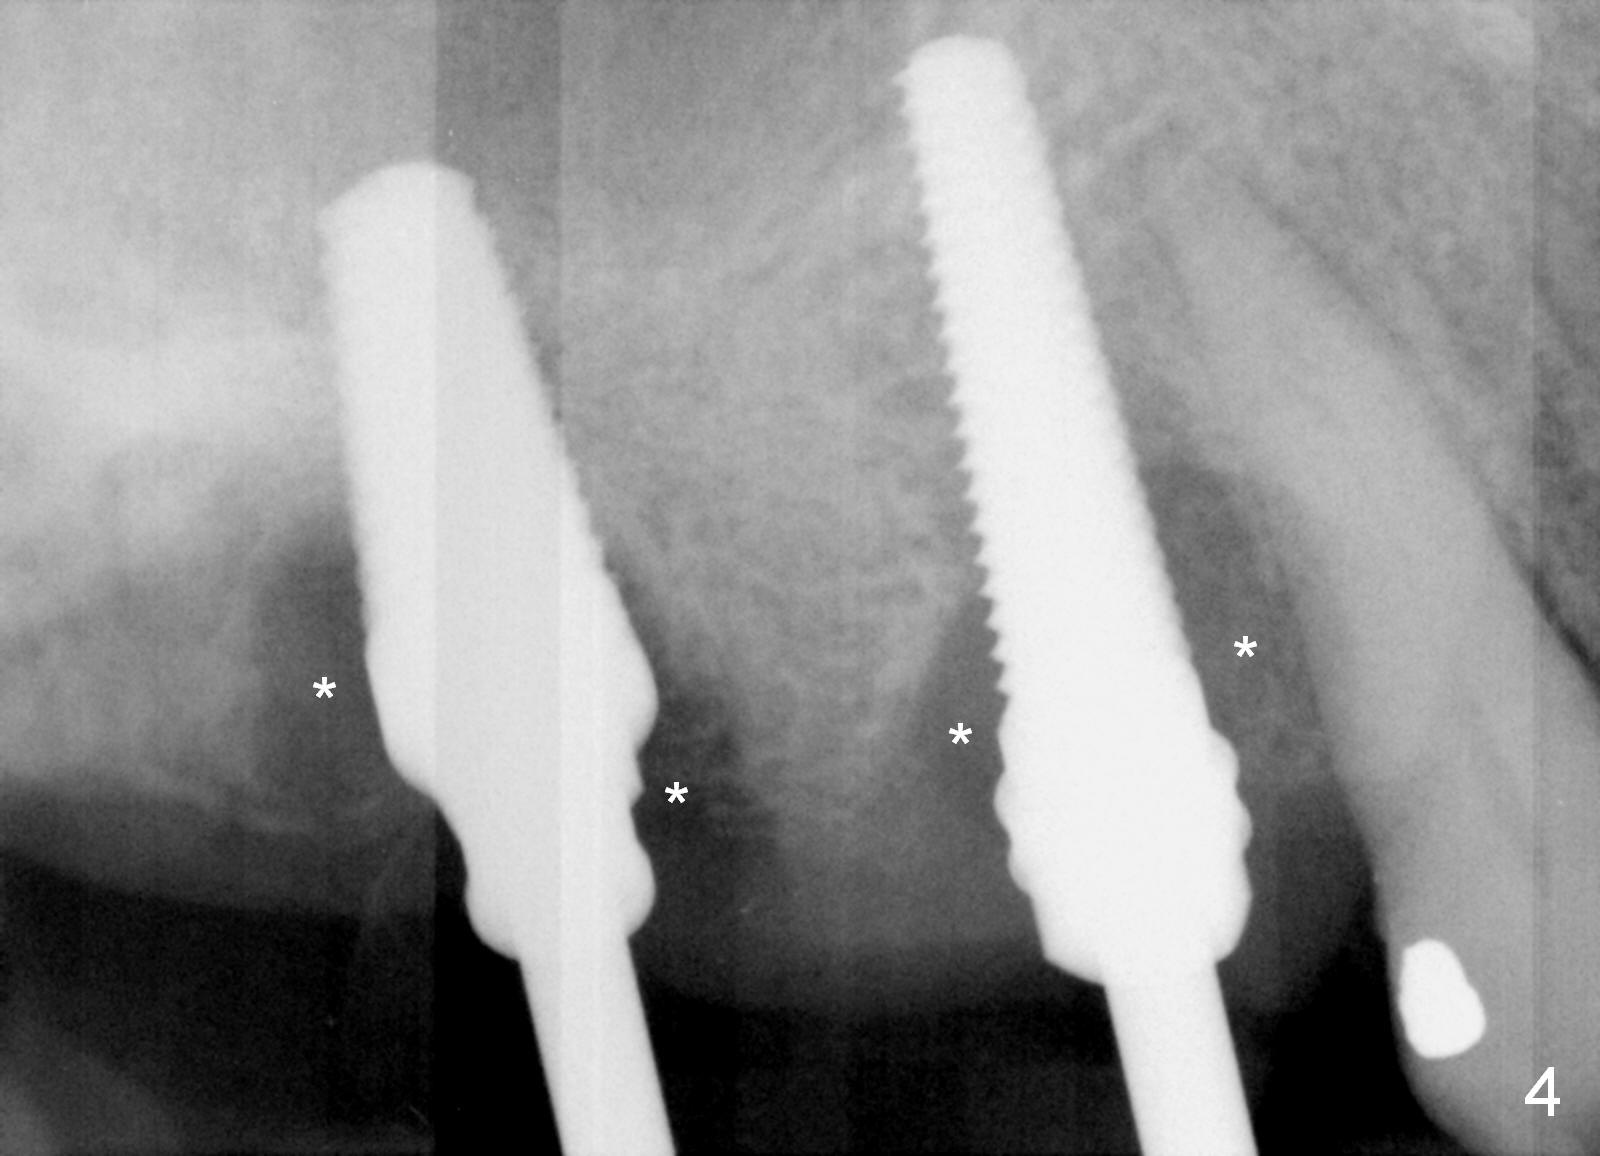

Preop photos show generalized gingival hyperplasia (hypertension med (Amlodipine, Calcium Channel Blocker), Fig.1 *), palatal (Fig.2<) and buccal (Fig.3 B) abscesses originated from the tooth #5. There is a smaller abscess buccal to the tooth #3 (not shown). After extraction, the buccal and palatal plates of the teeth #3 and 5 are found basically non-existent. When taps are placed, large socket defects are evident (Fig.4 *). In addition to sinus lift at #3 (Fig.5 black *), mineralized cancellous and cortical allograft (.5-1 and 1-2 mm) is placed around the implants with healing screws in place (white *). After the healing screws are removed and cemented abutments are placed, more allograft is packed (Fig.6-8 *). Closing the "dead" space in step may prevent immediately postop infection and peri-implantitis.